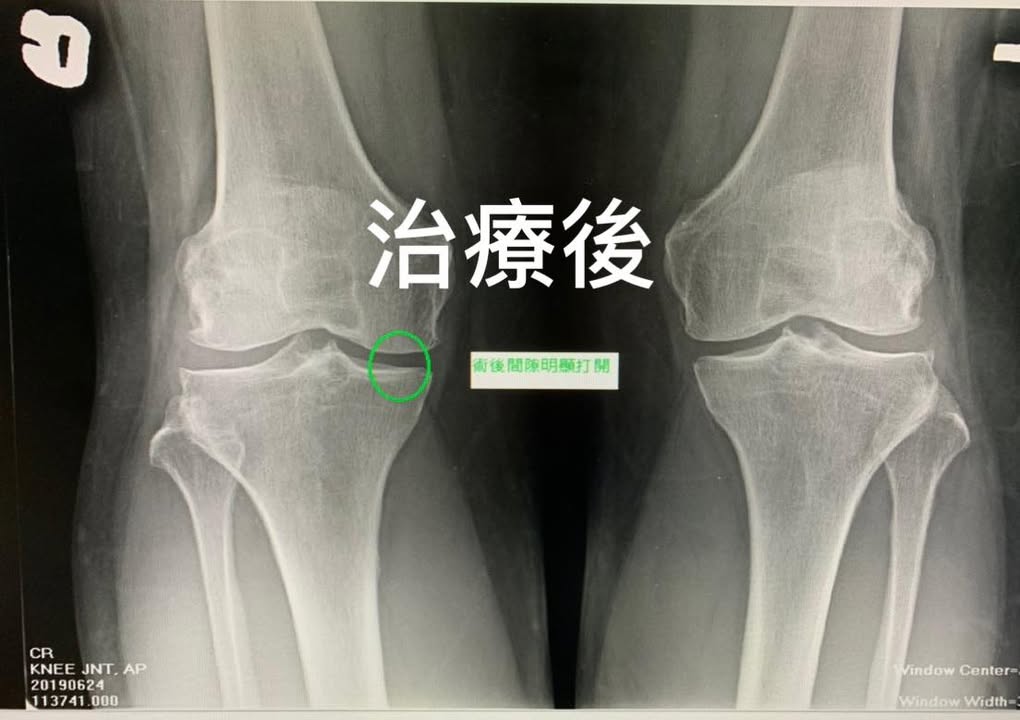

😢50多歲的王小姐膝蓋疼痛快半年,最明顯的症狀是膝關節蹲不下去,會有後側拉扯感,從座位轉成站位的姿勢很酸痛,上下樓梯也很酸痛,做過一兩個月的復健但是效果仍然不如預期,拍過X光片可以很清楚的看到右邊的膝蓋內側間隙過窄,這大約是退化性膝關節的第二到第三期,經過友人介紹接受膝關節整合治療,大約八週的時間,重新拍片檢查,在同一個檢驗所使用AP VIEW(正位照),兩張照片前後對比可以看到右側膝關節間隙明顯打開,兩張照片脛骨跟腓骨的交會角度幾乎是一樣,股骨跟脛骨的交會角度也是一樣,可以很大程度排除角度誤差,重點是臨床症狀幾乎完全消失,王小姐笑著說可以走路是一件很幸福的事情!!